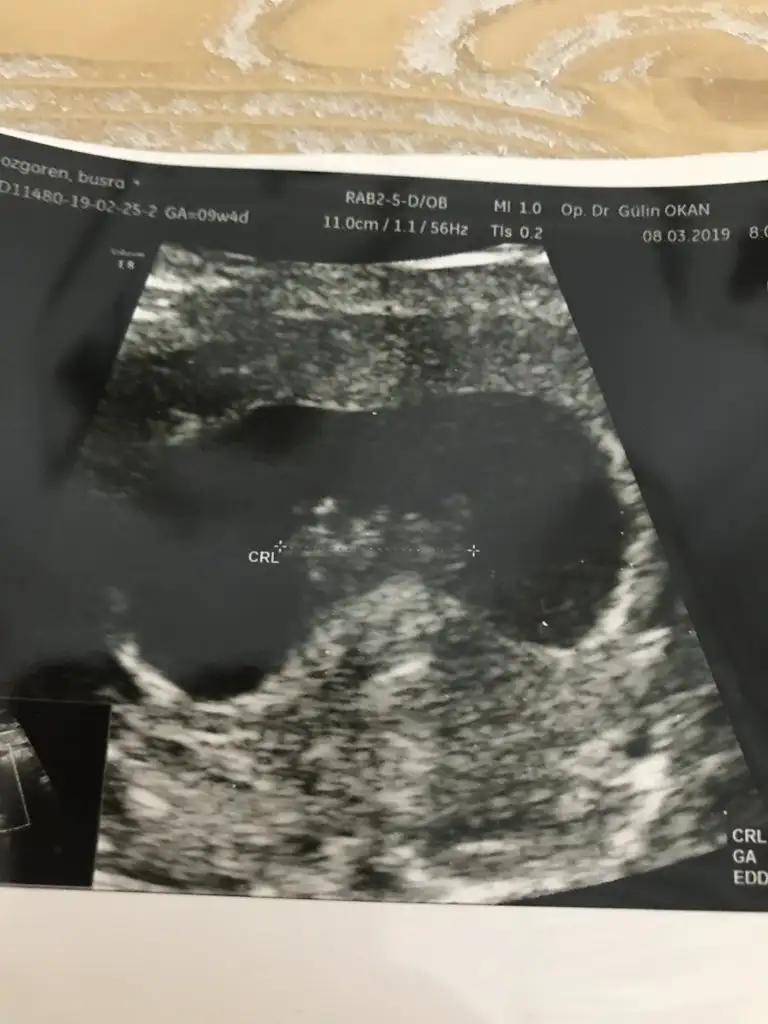

Merhaba canım bu 12 haftalık usg miz daha belli mi? Ya da fikri olan var mı

Kıza benzettim CanımArkadaşlar bana da yorum yapar mısınız lütfen 12 haftalık bebeğim